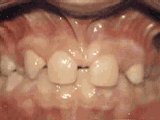

Phase I

Patient's parents were concerned about both aesthetics and the health of the erupting permanent teeth when they brought him to the orthodontist at age eight. The lower front teeth were crowded and they touched the palate, and the upper front teeth were extremely displaced from their normal positions. After twenty months of Phase I treatment with an expander and partial braces, patient's appearance and dental function was vastly improved.